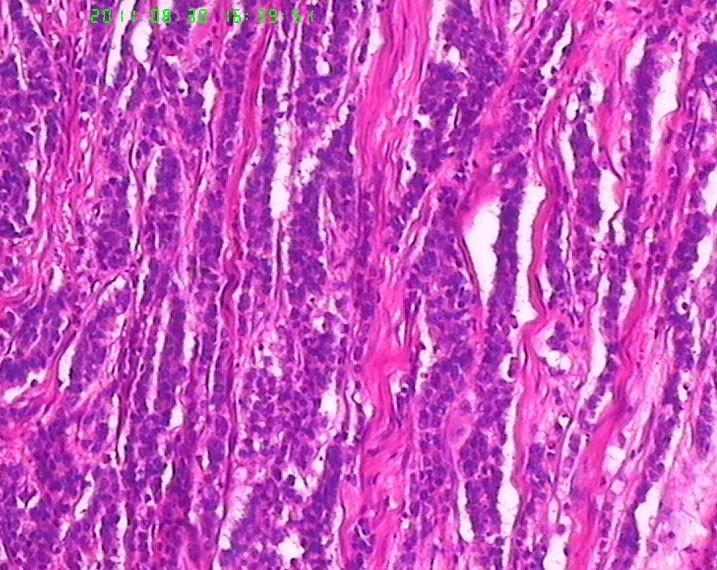

• 焦急:胃肿物,请老师帮看下。图3

图3

肿瘤呈流水线样排列,有腺样结构,核分裂像多见,从这些来说至少不是类癌了,如果是神经内分泌肿瘤,那也应该是神经内分泌癌了,此例可能为腺癌伴神经内分泌分化,需做免疫标记证实是否有神经内分泌分化。

若诊断管状腺癌,其中未见任何“管腺”形成迹象,故应诊断为“未分化腺癌”。但学生有以下疑问:1、为何肿瘤与正常胃粘膜交界处不见“非典型增生腺体”移行,而是截然交界。交界处可见淋巴细胞浸润。2、为何肿瘤浸润肌层的界面圆顿,如同“疣状癌”的膨胀性推挤生长。3、未分化腺癌恶性程度高,而为何胃周淋巴结检出二十余枚均未见转移。